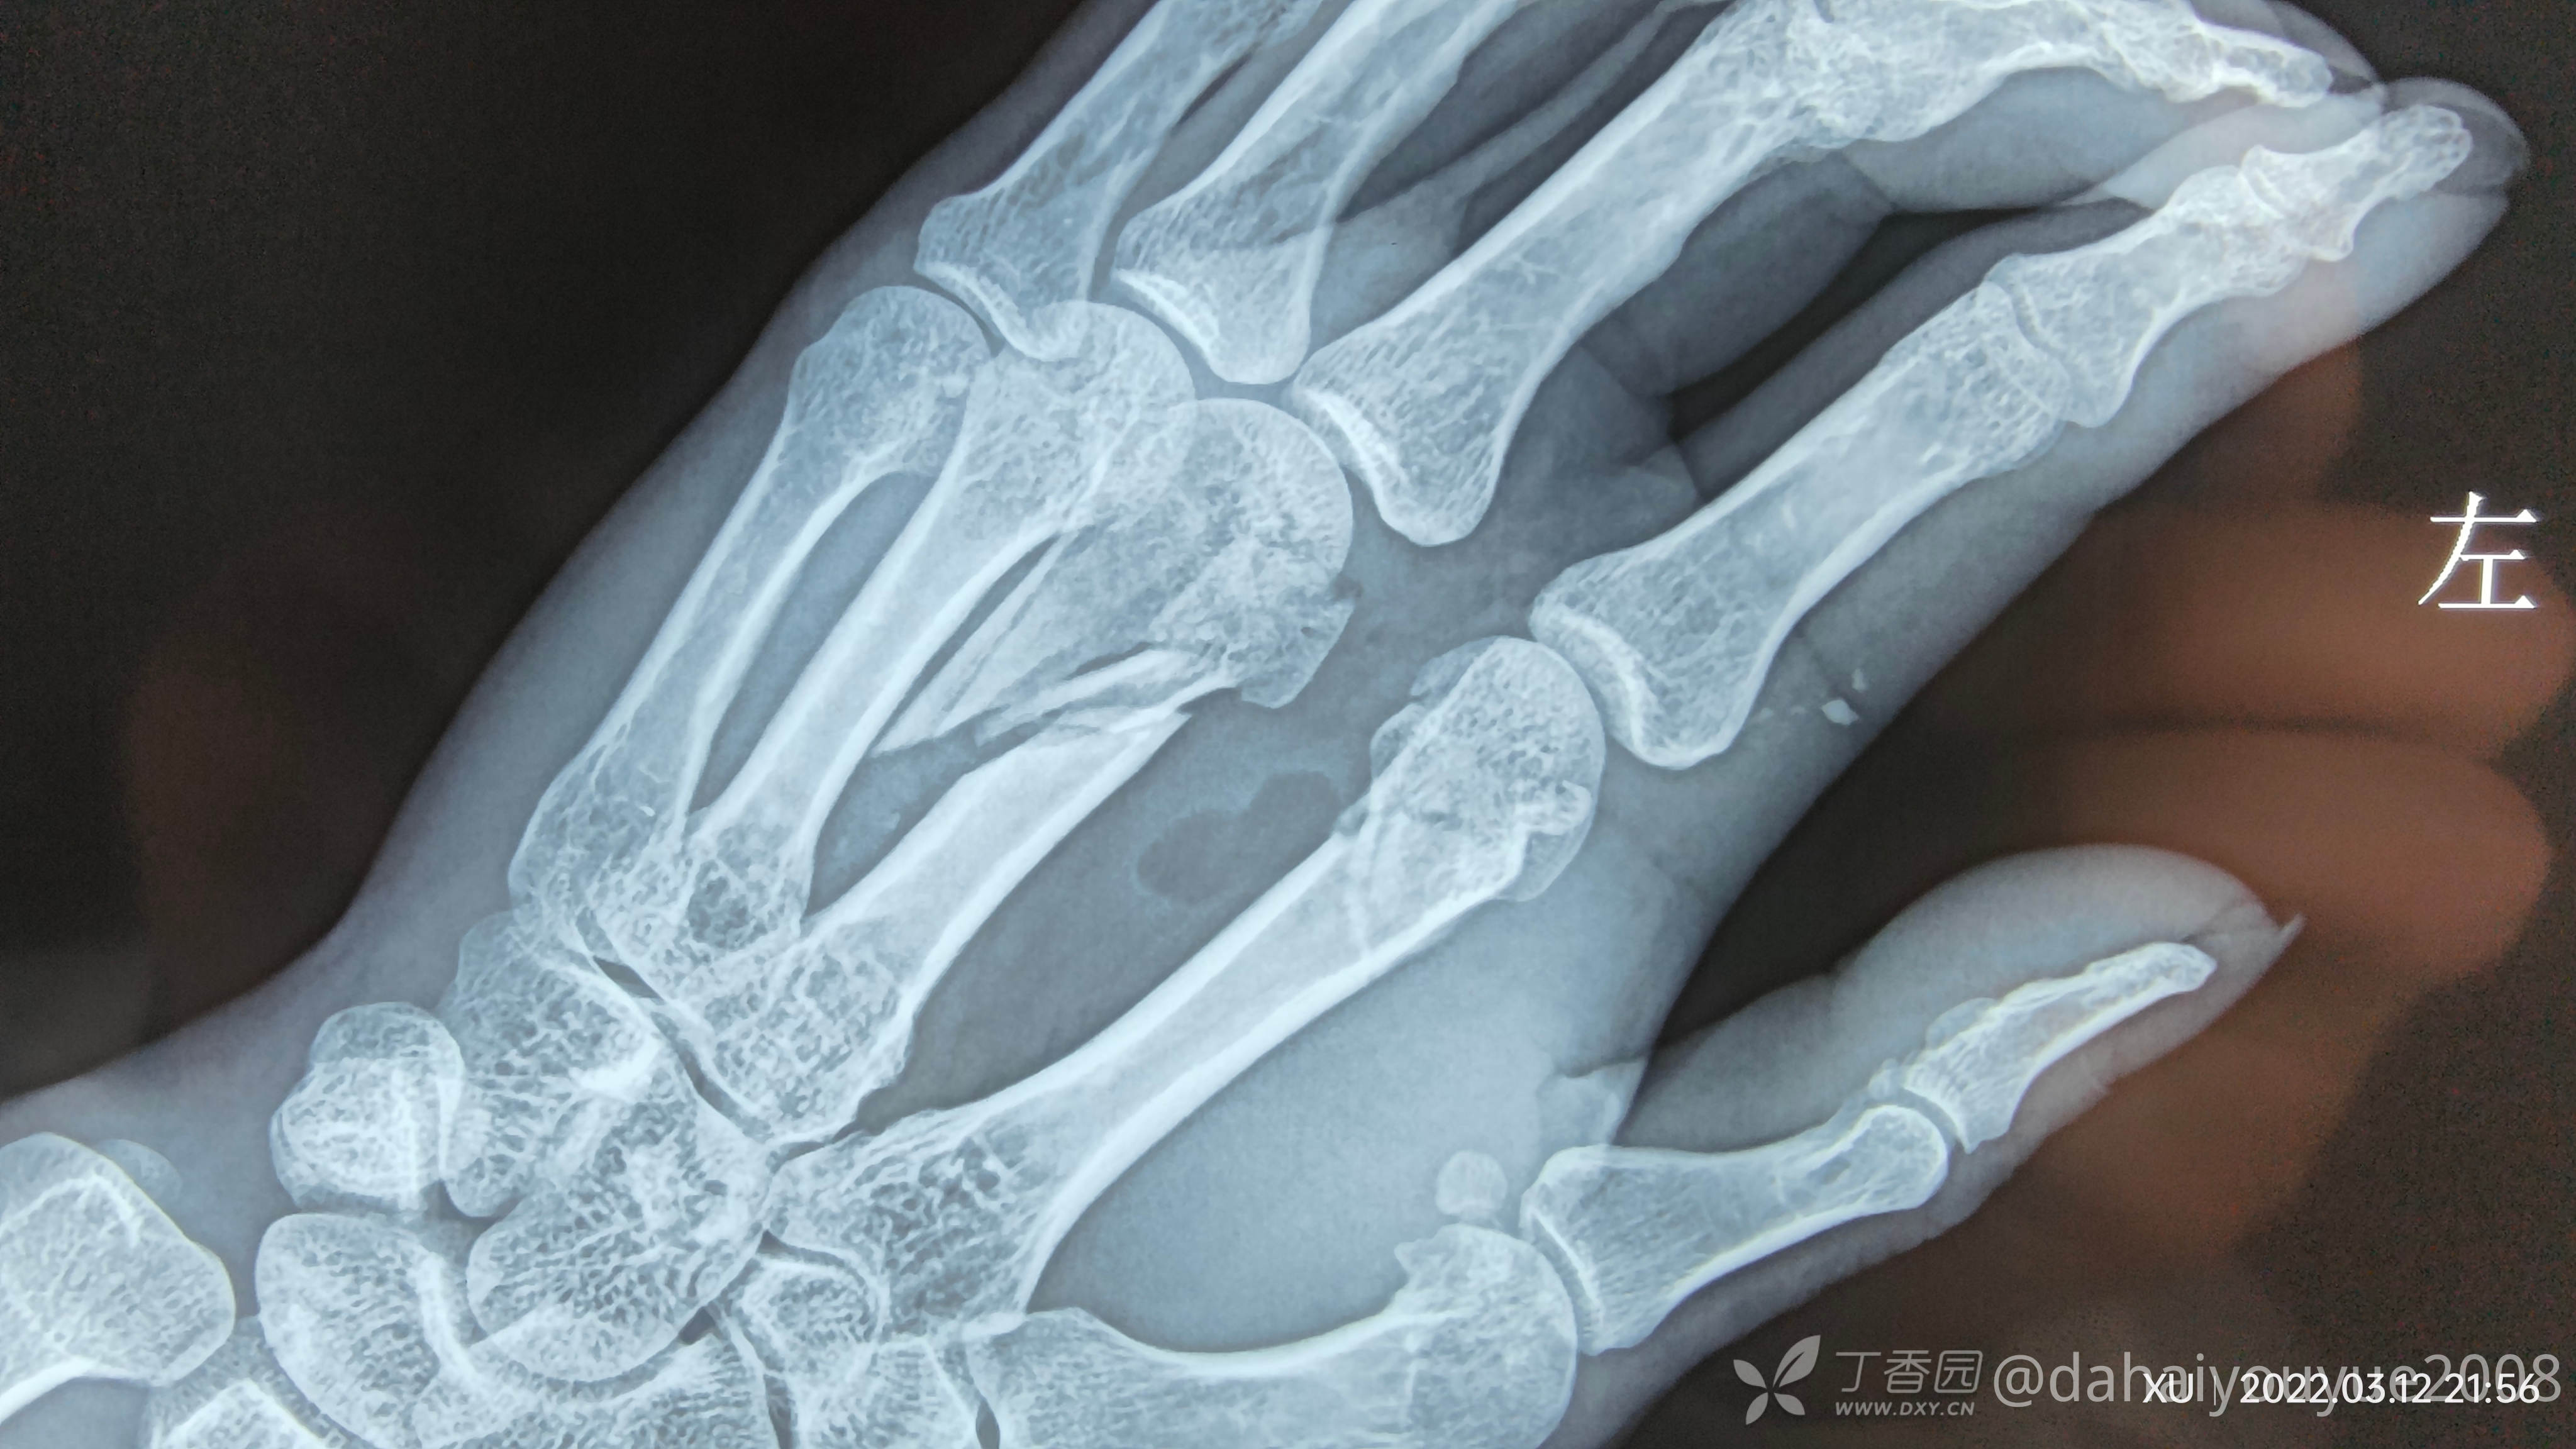

二,掌骨粉碎性骨折捆绑(术中未拍照片,术后效果还不错)